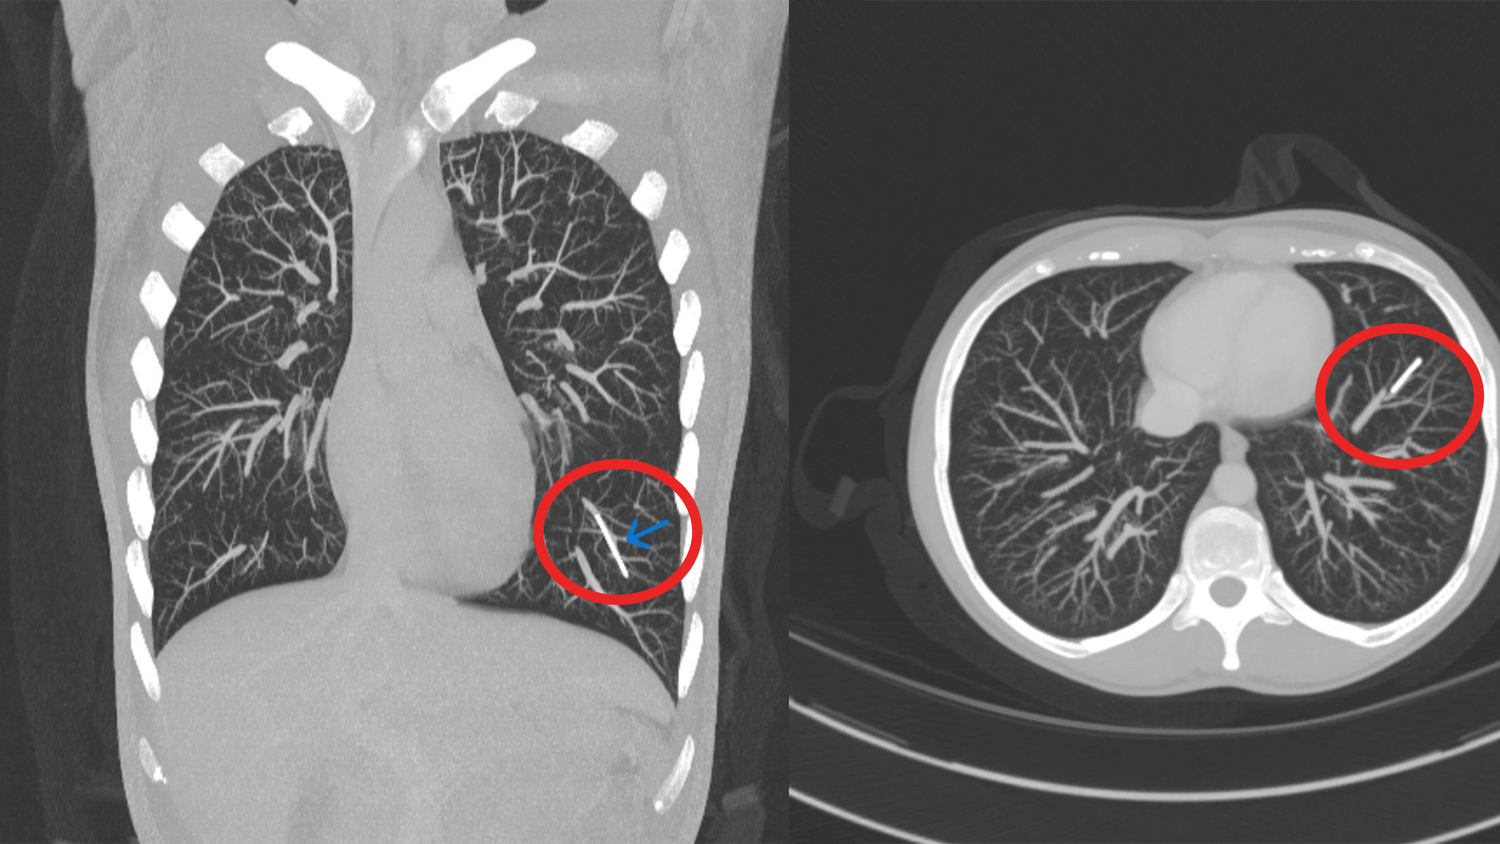

Dieses Verhütungsmittel kann in die Lunge "wandern"

Ärzte können es nicht finden

Schock für Frau – Verhütungsstäbchen wandert im Körper